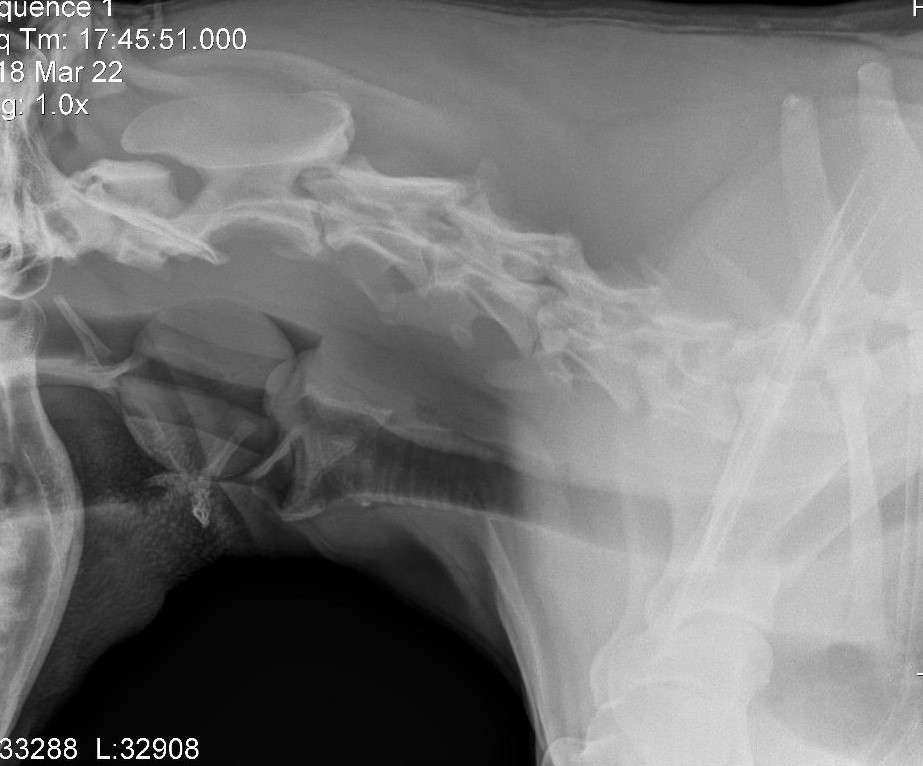

2019 They Ate What?! X-ray Contest winnersThey Ate This: Check out the winner, runners-up, and honorable mentions September 30, 2019 < Previous Entry Next Entry > Pages: 1 2 3 4 5 6 7 8 9 10 11 12 13 14